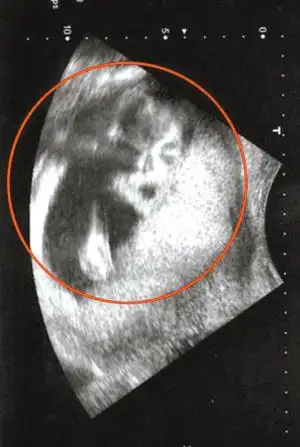

b超检查怀孕50天同卵双胞胎是这样的,孕妈看看你的双胞胎儿吧

戴娇倩承认怀孕 晒b超图:新的身份,新的生命